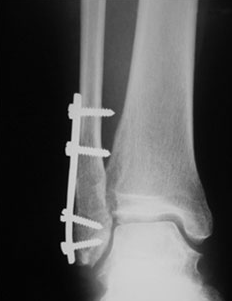

발 관절이 강하게 바깥쪽으로 비틀어지게 되면 거골에 밀려 외과골절이 발생할 수 있고, 이는 나선형으로 꺾이는 경우가 많습니다. 뼈가 어긋남이 없다면 깁스등의 보존적 치료가 가능하며, 어긋남이 심하다면 플레이트와 나사등을 이용하여 고정하는 수술을 할 가능성이 있습니다.